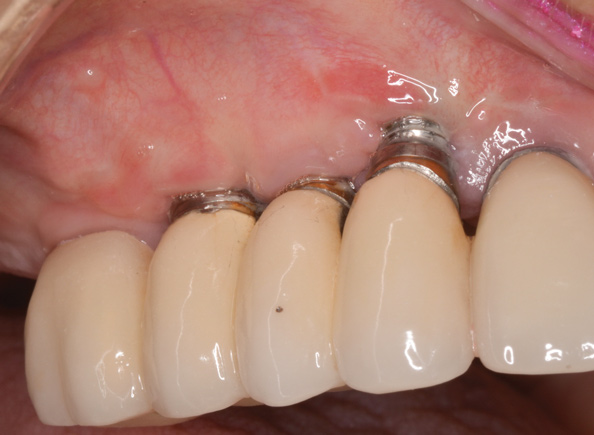

(11.) Implants placed too far towards the facial aspect of the ridge. With excessive pressure from the abutments and an ill-fitting prosthesis, implant therapy has failed. The facial bone is deficient, and there is significant mucosal recession and lack of keratinized tissue.

Figure 11

(12.) Implants placed too far towards the facial aspect of the ridge. With excessive pressure from the abutments and an ill-fitting prosthesis, implant therapy has failed. The facial bone is deficient, and there is significant mucosal recession and lack of keratinized tissue.

Figure 12